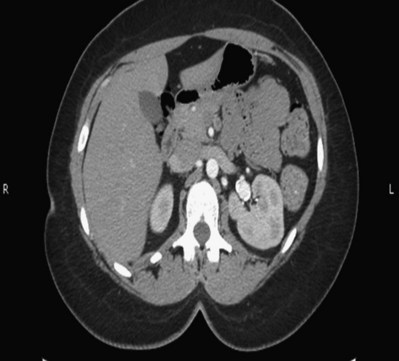

Three-dimensional (3D) volume-rendered CT is a valuable tool in the evaluation of patients undergoing renal surgery (Coll et al, 1999; Derweesh et al, 2003). CT can demonstrate vital information including the anatomy of the renal vasculature, orientation of the kidney, and characteristics of renal tumors, including location, depth of penetration into the kidney, relationship with collecting system, and segmental arterial supply to the tumor (Coll et al, 1999) (Figs. 54-12 to 54-14). CT is also able to characterize other surgically relevant processes, including renal arterial disease, nephrolithiasis, and hydroureteronephrosis (Herts, 2005).

Figure 54–12 Contrast-enhanced CT axial reconstruction demonstrating large right hypervascular mass suggestive of renal cell carcinoma.